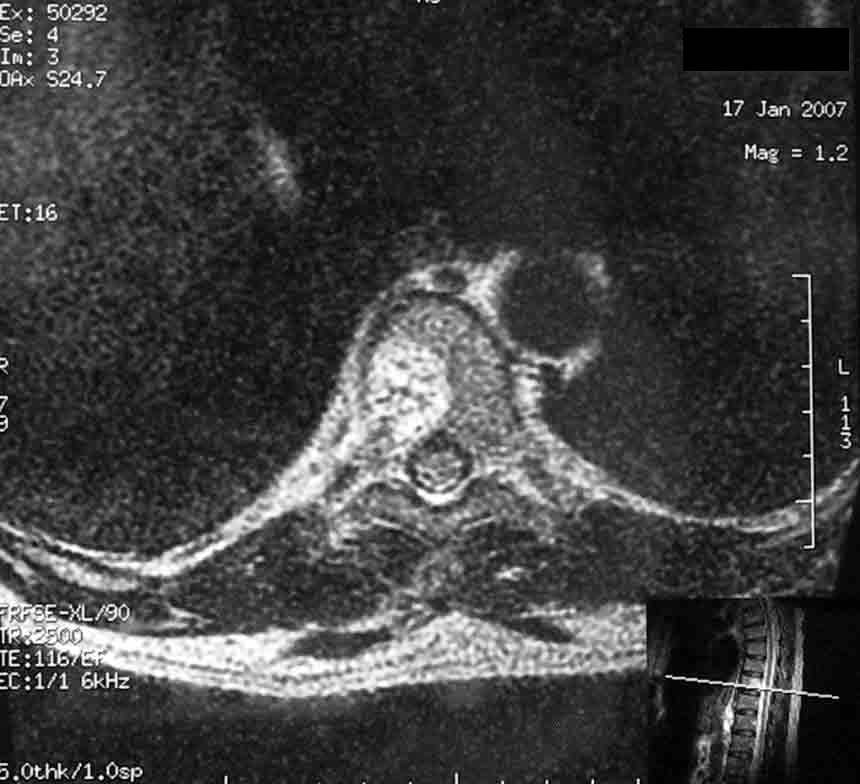

У пациентки 50 лет, сотрудницы нашего центра проводили обследование по поводу хронических болей в поясничном и грудном отделе позвоночника.

Помимо распространённого остеохондроза и деформирующего спондилёза обнаружили гемангиому 1/2 тела Th-9 позвонка.

Какова может быть тактика лечения гемангиомы? Локальной болезненности при пальпации 9-го грудного позвонка нет, боли носят распространённый характер, не привязаны к Th-9.